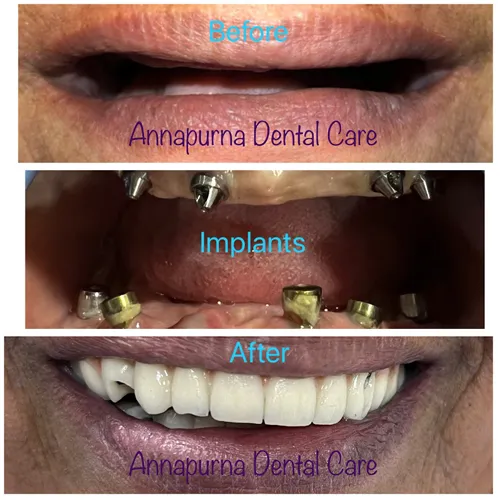

DENTAL IMPLANTS

Dental implant surgery is a procedure that replaces tooth roots with metal, screwlike posts and replaces...

Read More